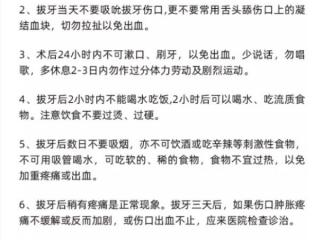

1. 拔牙后恢复过程

拔牙后会形成拔牙窝,半小时后会形成一个血凝块,血凝块是保护伤口的,也是加速拔牙创伤愈合的。

小知识:拔牙窝的恢复是从凝血块开始的,拔牙后24小时左右局部的「纤维母细胞」刚从牙槽骨壁向血凝块延伸生长,并逐渐使血凝块机化而变得坚固结实。

但血凝块的生长需要一个过程,刚凝结而成的血凝块,很嫩,质感犹如嫩豆腐,也很容易被破坏。

如果拔牙当天吐口水、漱口,会导致口腔内负压产生,很容易将血凝块吐掉,从而导致出血不止,没有血凝块的保护拔牙的伤口会发炎,很容易形成干槽症,产生剧烈疼痛!

干槽症

拔牙后血凝块脱落牙槽骨暴露,呈现出干燥表面,暴露于充满细菌的口腔中,而发生骨壁感染。正常的拔牙窝愈合,是牙齿拔出后,血块充填牙槽窝机化形成新生组织。

伴随干槽症的,是拔牙后3-5天的难以忍受的疼痛,甚至放射于同侧耳朵、太阳穴的痛是最无法忍受的,这种疼痛的可怕之处在于吃了止痛药效果也不好。

那么,如何判断自己是正常的术后反应还是干槽症呢?我们要注意以下几个关键点。

首先,出现的时间,不是拔牙后就立刻出现,也就是说拔除智齿后前两天出现上述症状无需紧张,可观察症状的发展。其次,是疼痛的区域,如果只局限在拔牙窝,可能只是术后反应。

再次,就是从止痛药是否能缓解症状来判断,如果无效,那么就要去找医生了。当然,医生还会有看、探等专业动作来确诊干槽症。

得了干槽症可就比较麻烦了,必须得到牙科医生或口腔外科医生的合理治疗,才会慢慢好起来,愈合时间大大延长还非常痛苦。

所以,医生叫你不要吐口水,就乖乖听话,有口水就轻轻咽下去。

2. 那口水太多又怎么办呢?

拔牙后24小时内若口水太多,轻轻咽回去,血不止牙齿是不会痊愈的。

第一天流血很正常,但大量的出血就要看医生了。

第二天有少量血丝也属正常,不能刷牙但可轻轻漱口了。

第三天以不出血为好,若还出血就要注意了,漱口一定要用消炎漱口水。

拔牙虽然是一个很常见的口腔治疗,但是严格上说也是一项手术,关系着口腔健康和全身健康,各位宝宝一定要认真听医生的话,按照医嘱,认真做好术后护理!